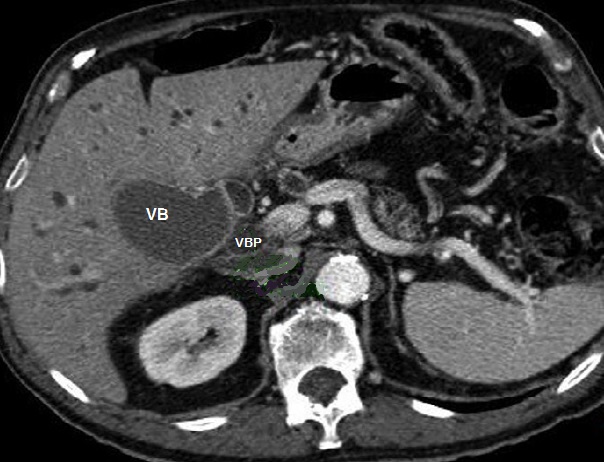

Une autre cas de

adenocarcinoma de la tete du pancreas avec image de

dilatation important du canal pancreatique

principale ( CPP ) et canal biliaire principale (

CBP ) se donne image de "double duct sign " .

Image de dilatation des voies biliaires

intrahepatique est encore en vue . Coupe TDM axiale

a travers L2 |

Signe "Double-duct sign"

d'unre adenocarcinoma de la tete du pancreas ,

dilatation marquee du canal biliaire principale et

image de dilate important du canal pancreatique CPP

. Image radiologique Wirsungo-cholangio IRM |